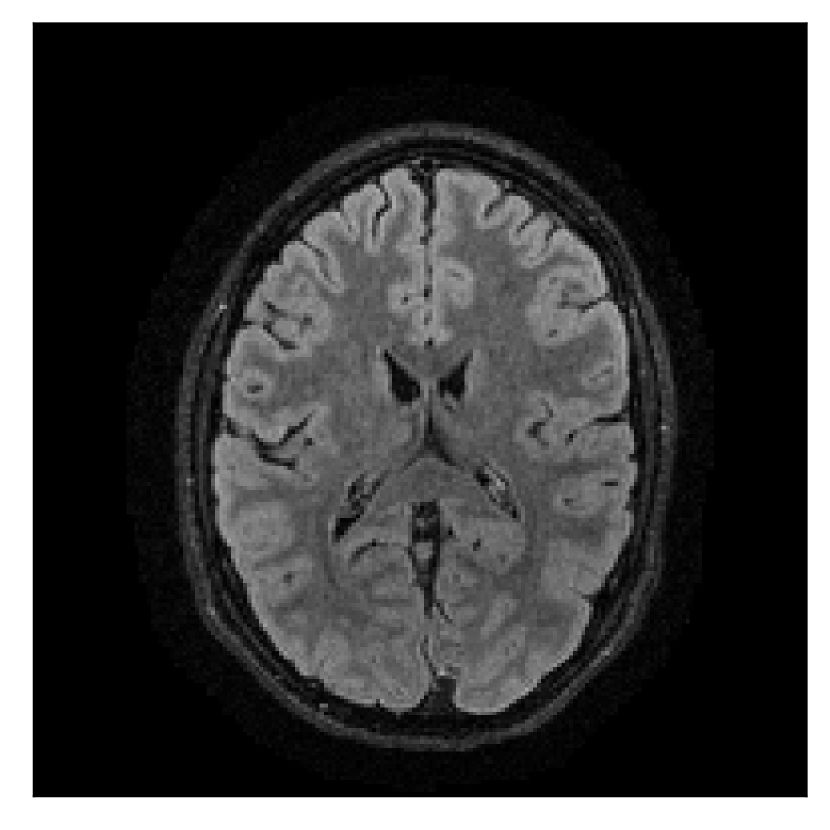

We consider three levels of motion corruption: (i) the volunteer moves once, (ii) the volunteer moves twice, and (iii) the volunteer moves five times. The volunteer is instructed to change its head position every time it is prompted to do so, and maintain that position in between instructions. We use T2-FLAIR-weighted contrasts as corrupted scans, with T1-weighted contrast as a reference (see Table 1 for further details). The corrupted acquisition employs randomized sampling.

4.1 Experiment 1: robustness test

We gather the results for the robustness test described in Section 3.1 (volunteer 1) in Figures 2, 4, and 6 for motion corruption mechanisms associated to one, two, and five changes of position, respectively. Furthermore, we juxtapose the corrected images with varying degrees of corruption in Figure 8. We observe that the proposed method consistently ameliorates the corrupted scan. The quality indexes based on PSNR and SSIM show only a modest decrease in correction quality as a function of motion complexity (Figure 8).

| Section 3.1, Figure 4 | Sagittal | 25.78 | 27.76 | 0.7263 | 0.7816 |

| Coronal | 28.19 | 29.73 | 0.7847 | 0.8244 | |

| Axial | 27.79 | 29.70 | 0.8104 | 0.8362 | |

| Section 3.1, Figure 4 | T2-FLAIR | Completely corrected | Some blurring | No additional artifacts | Good grey white matter differentiation |